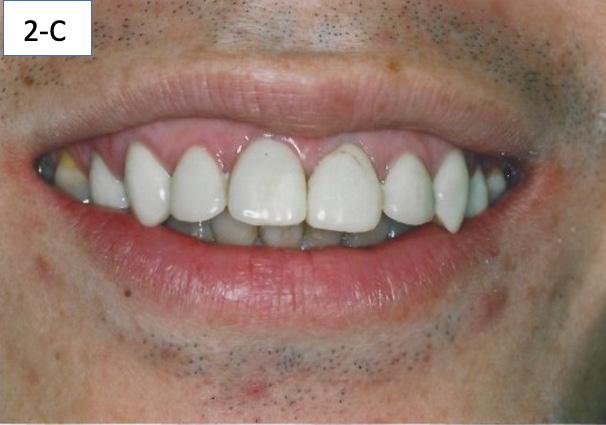

Clinical Mini-esthetic appraisal revealed full upper and lower lips incompetent and incongruent smile arc to the lower lip. The patient’s posed smile revealed positive buccal corridors and adequate tooth display at lips in repose. (Figure 2-A, B, C).

FIG. 2A: Pre-treatment, lips together

FIG. 2B: Pre-treatment, lips in repose

FIG. 2C: Pre-treatment posed smile